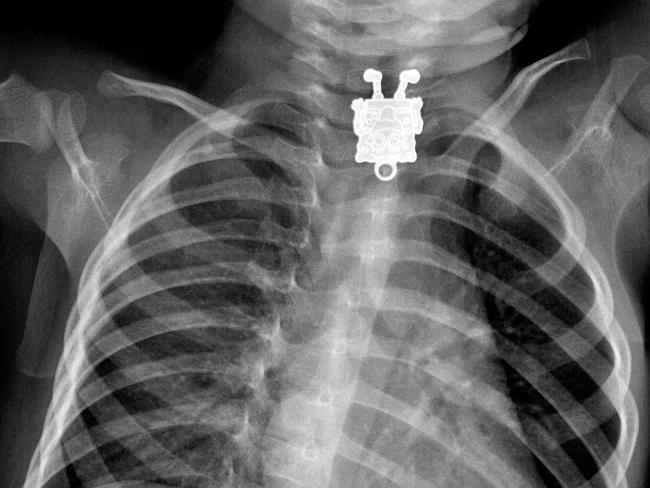

Cientos de objetos fueron introducidos por los estadounidenses en sus cuerpos durante 2017 y el portal Deadspin recopiló una lista con los elementos más extraños que las personas no pudieron sacar de sus orificios por lo que recurrieron a salas de emergencia.

El listado fue elaborado sacando los datos de los registros públicos de las visitas a urgencias en el país, publicadas por la Comisión para la Seguridad de los Productos de Consumo de Estados Unidos (NEISS).

Allí se detallan las cosas por cada parte del cuerpo y destaca la preocupante cantidad de objetos que las personas ingresaron a través de sus rectos.